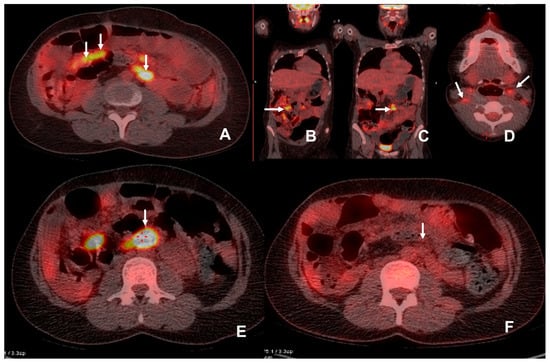

Figure 4. The patient was admitted with an elevated amylase level 6 years post multivisceral transplant. CT demonstrated increased prominence of mesenteric lymph nodes and there was a clinical suspicion of PTLD. 18F-FDG PET/CT demonstrated multiple FDG avid (SUVmax 12.6) mesenteric lymph nodes (white arrows)(AC). Biopsy demonstrated a monomorphic plasma cell infiltration in keeping with PTLD. Anti-rejection/immunosuppressant therapy was reduced in an attempt to control the PTLD. Follow-up 18F-FDG PET/CT examination was performed at 2.5 months (D,E) due to an inability to biopsy the deep-seated lymph node in a difficult abdomen with significant thrombocytopenia. This showed a marked increase in SUV (SUVmax 23.7) and the size of the mesenteric lymph nodes, a large FDG avid para-aortic lymph node (white arrow with adjacent red crosshairs, image (E)) and additional involvement of cervical lymph nodes (white arrows, image (D)) with SUVmax at 4.6, in keeping with progressive PTLD. Results of this examination were discussed at MDT and Rituximab was commenced. A further follow-up 18F-FDG PET/CT was performed 10 weeks after the initiation of Rituxiamb and demonstrated resolution with a significant drop in SUV (F) for the reference nodes.